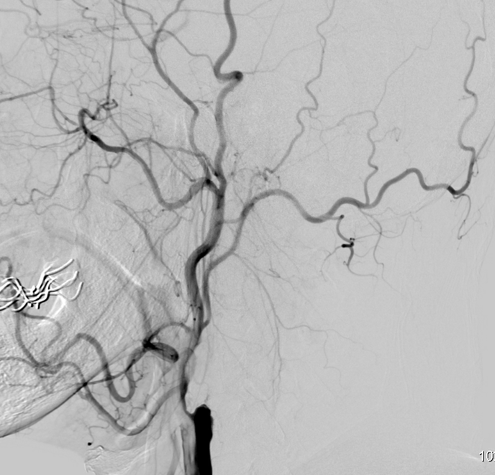

患者男性71岁,因“头晕伴左侧肢体无力3月”入院,就诊于我院神经外科。头颅CT提示:1.多发腔隙性脑梗塞2.右侧基底节及外囊区梗塞。行全脑血管造影(DSA)提示右侧颈内动脉起始段闭塞,颅内段血管显影不佳。患者高龄,既往有高血压、糖尿病、高脂血症、心脏病等、病情复杂。如不及时予以治疗,将可能发展为大面积脑梗塞,危及生命。王晓健副主任医师团队详细分析患者资料后,结合相关文献并借鉴国内先进单位成熟技术,决定对患者实施闭塞颈动脉开通术(CEA+颅内外支架植入的复合手术)。切开颈内动脉,剥除斑块,同时在颈内动脉狭窄段放入支架。术后造影显示闭塞动脉开通满意,血管通畅,患者恢复良好,3—4天后即可在辅助下行走,一周后就已顺利出院。

术后DSA